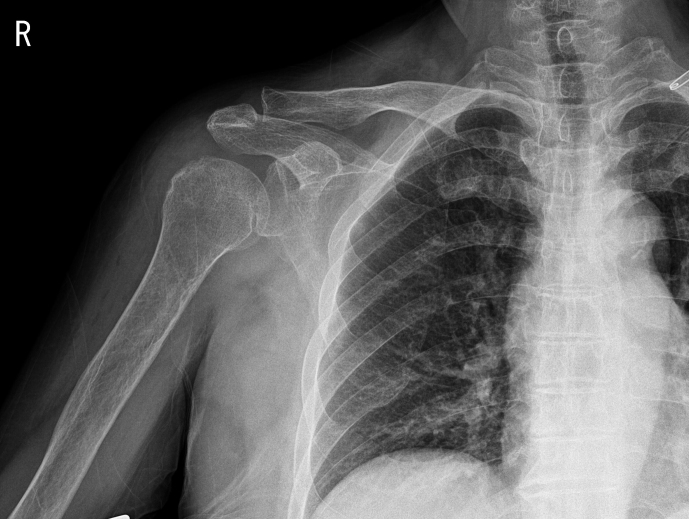

Moraxella catarrhalis commonly colonizes the upper respiratory tract of humans, but infection caused by M. catarrhalis after orthopedic surgery is rare. Here, we report the first case of septic arthritis of the shoulder caused by an M. catarrhalis infection and outline the diagnosis and treatment steps as well as differences compared with other cases.